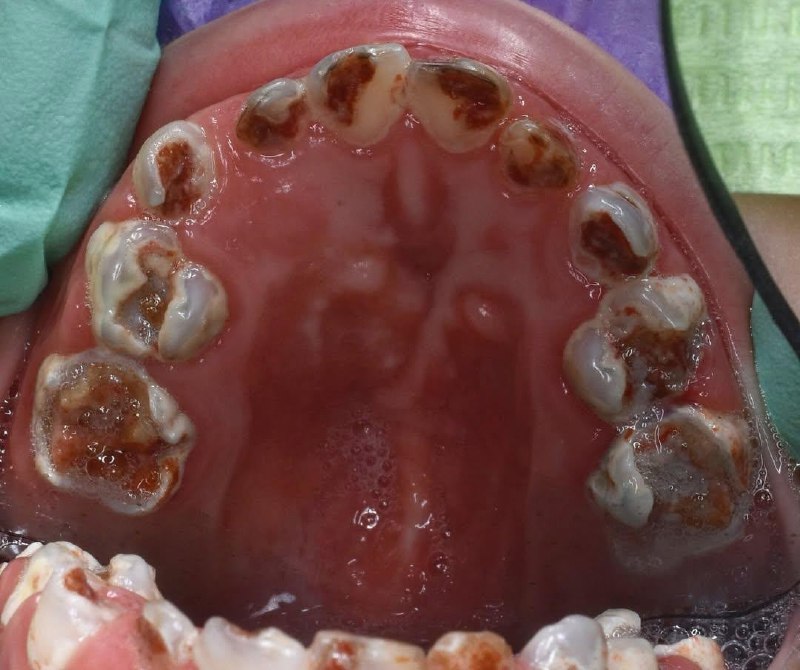

⚡️Протокол восстановления нижнего 1 моляра ❗️Мы в MAX - CreativeDentistry

1 мар. 2026 г.

2.2k 29 48